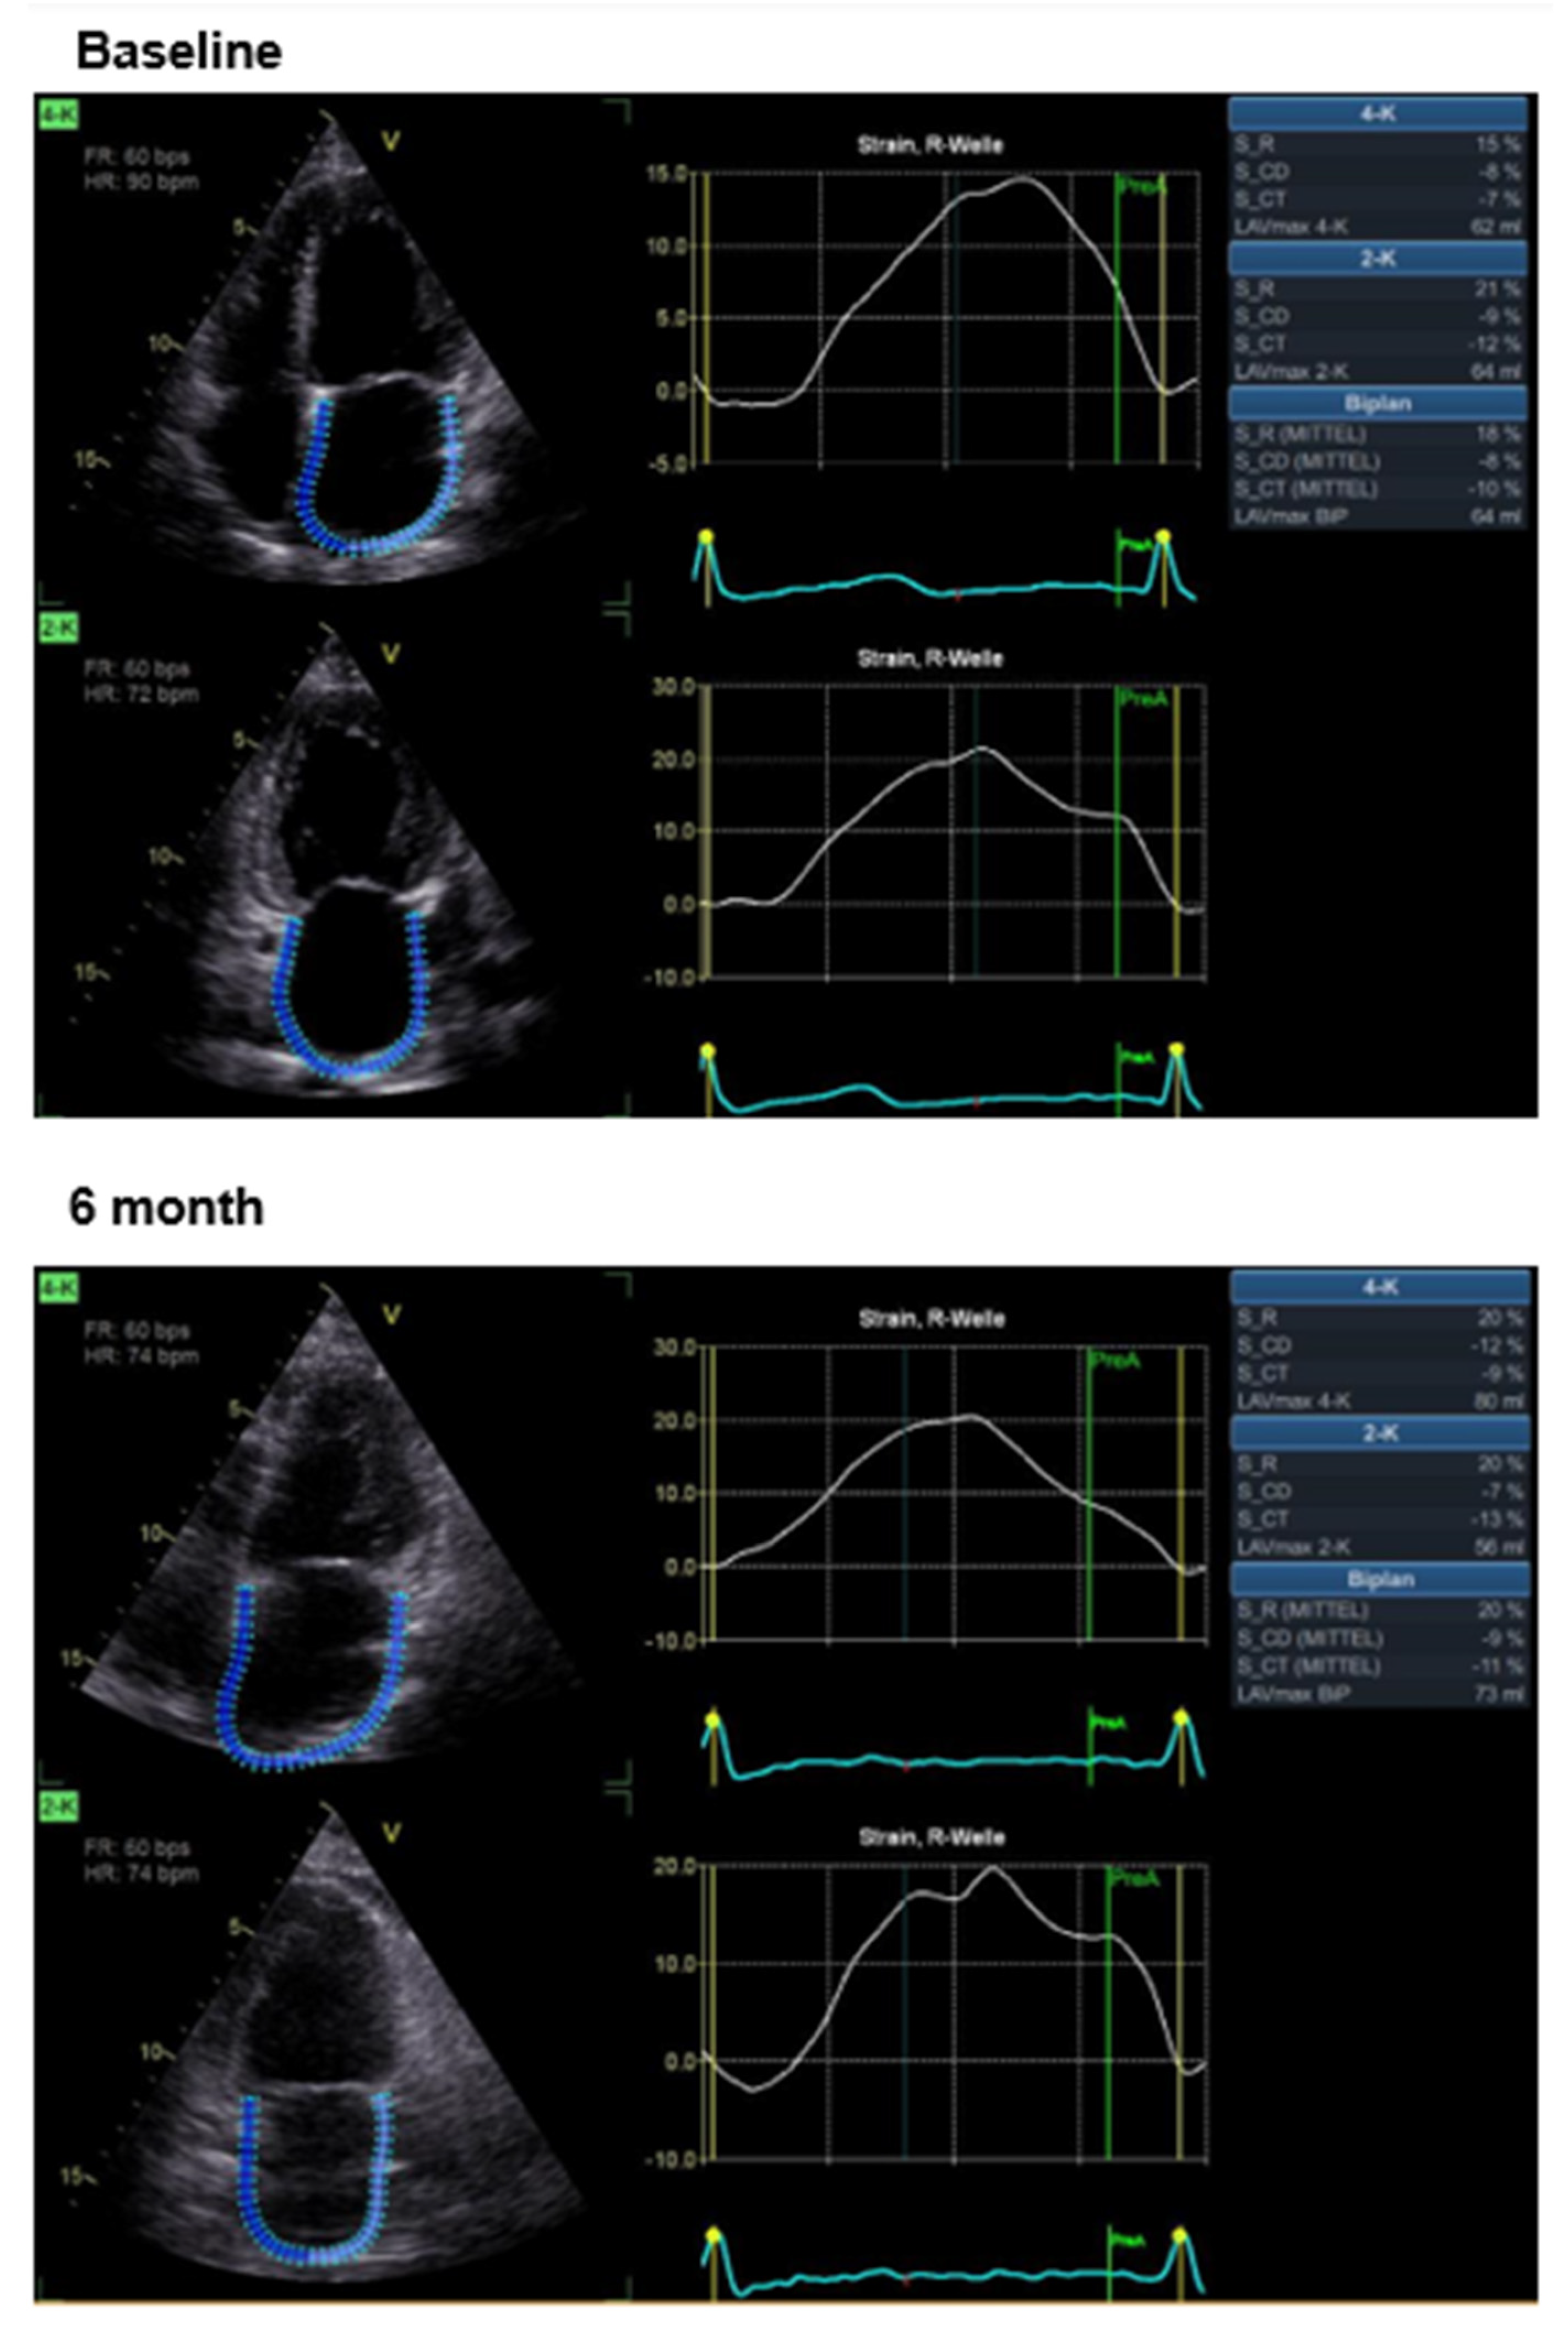

Effects of CCM Therapy

| LA S_R [%] | 19.7 ± 1.0 | 15.3 ± 10.2 | <0.05 |

| LA S_CD [%] | −9.0 ± 5.0 | −8.1 ± 5.4 | n.s. |

| LA S_CT [%] | −11.5 ± 7.0 | −7.1 ± 8.5 | <0.05 |